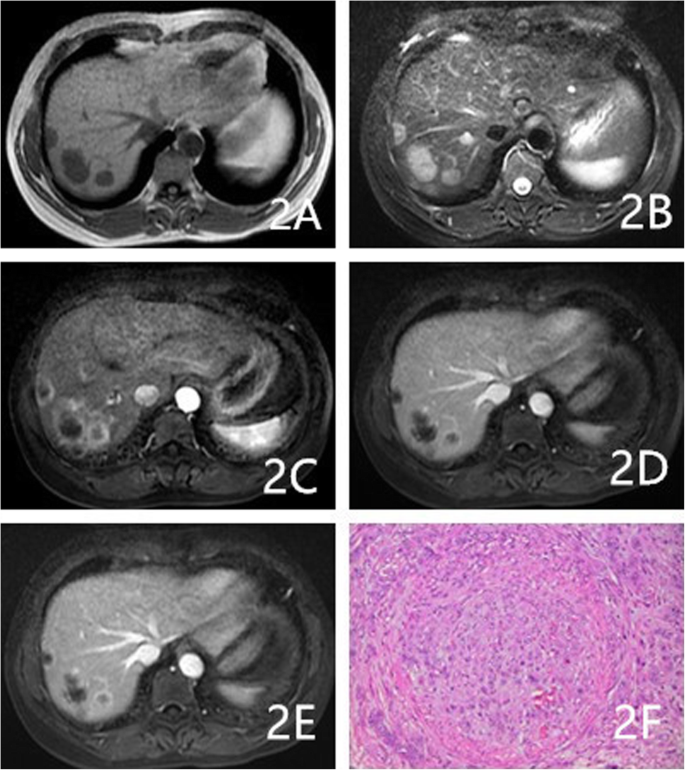

A 53-year-old female had multiple HEHE lesions in the right hepatic lobe. a-b: Multiple homogeneous signal masses were observed on T1WI and T2WI. c-e: The enhanced scan showed rim enhancement in the arterial phase and progressive centripetal enhancement in the portal and delayed phases. f: Magnification 200×. Epithelium-like tumor cells were closely arranged. A few lumens and RBCs in the lumen were observed

As Table 2 shows, the proportions of cases with circumscribed margins were 88% (22/25), 84.6% (11/13), and 31.6% (6/19) for hemangioma, HEHE, and HAS, respectively (P < 0.001). The differences among these groups were significant, and HAS lesions were more likely to not have circumscribed margins. The proportions of lesions with hemorrhaging were 4% (1/25), 30.8% (4/13), and 36.8% (7/19) for hemangioma, HEHE, and HAS, respectively, (P = 0.014). The proportions of cases with homogeneously low T1WI signals were 72% (18/25), 46.1% (6/13), and 21% (4/19) for hemangioma, HEHE, and HAS, respectively (P = 0.004). HEHE and HAS were more likely to show heterogeneous signals on T1WI (Figs. 1a, 3a, and 4a). The proportions of cases with homogeneously high signals on T2WI 64% (16/25), 23.1% (3/13; Fig. 2b), and 10.5% (2/19) for hemangioma, HEHE, and HAS, respectively (P = 0.001). HEHE and HAS were more likely to show heterogeneous signals on T2WI. Centripetal enhancement was the common pattern in vascular tumors, with proportions of 100, 46.2% (6/13), and 68.4% (13/19) for hemangioma, HEHE, and HAS, respectively (Figs. 3b-d and 4c-e). The difference in the enhancement pattern between the HEHE and HAS groups was significant(P < 0.001), and rim enhancement was common in cases of HEHE (46.2%, 6/13; Figs. 1c-e, 2c-e). In addition, three cases of HAS (15.8%, 3/19) showed no enhancement in any of the phases.